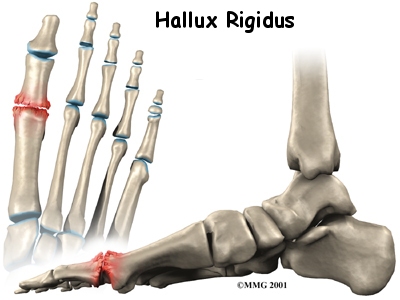

Hallux rigidus is a degenerative type of arthritis that affects the large joint at the base of the big toe (sometimes called the great toe). Degenerative arthritis results from wear and tear on the joint surface over time. The condition may follow an injury to the joint or, in some cases, may arise without a well-defined injury.

The big toe in medical terms is called the hallux. The joint at the base of the big toe is called the metatarsophalangeal, or MTP, joint. Like any other joint in the body, the joint is covered with articular cartilage, which is a slick, shiny covering on the end of the bone. If this cartilage is injured, it begins a slow process of wearing out, or degeneration. The articular surface can wear away so much that eventually raw bone rubs against raw bone.

Bone spurs form around the joint as part of the degenerative process. The spurs, or bony outgrowths, may restrict the motion in the joint, especially the ability for the toe to bend upward as the body moves forward over the foot, such as when you are taking steps. The big toe becomes very stiff or immobile into this range of motion, hence the reference to rigidity in the name of this condition.